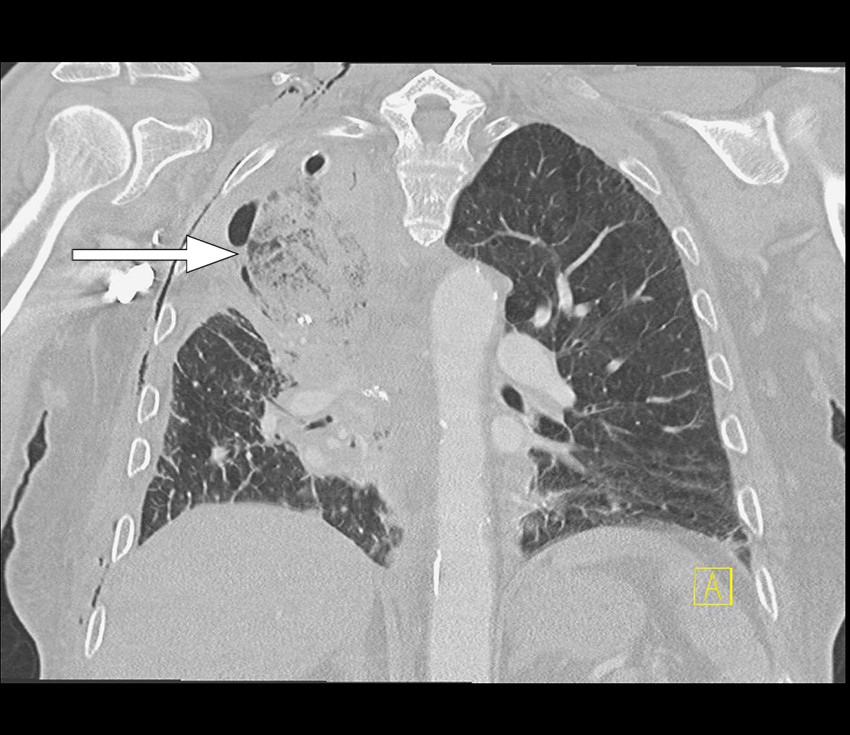

Grunnet tettere oppfølging ble røntgen toraks utført senere samme dag. Denne viste ikke vesentlig endring. Pasienten ble derfor henvist til CT-undersøkelse for videre diagnostikk. CT toraks med intravenøst kontrastmiddel utført på kveldstid samme dag viste en apikalt lokalisert midtlapp med utbredte mattglassfortetninger og områder med konsolidering samt fortykkede interlobulære septa (figur 2). Midtlappen fremsto som nærmest fullstendig devaskularisert. Proksimale midtlappsbronkus var obliterert, og transversale snitt viste subtilt virveltegn (swirl sign) i midtlappen som tegn på vridning. Fra radiologisk hold ble det reist mistanke om torsjon av midtlappen.